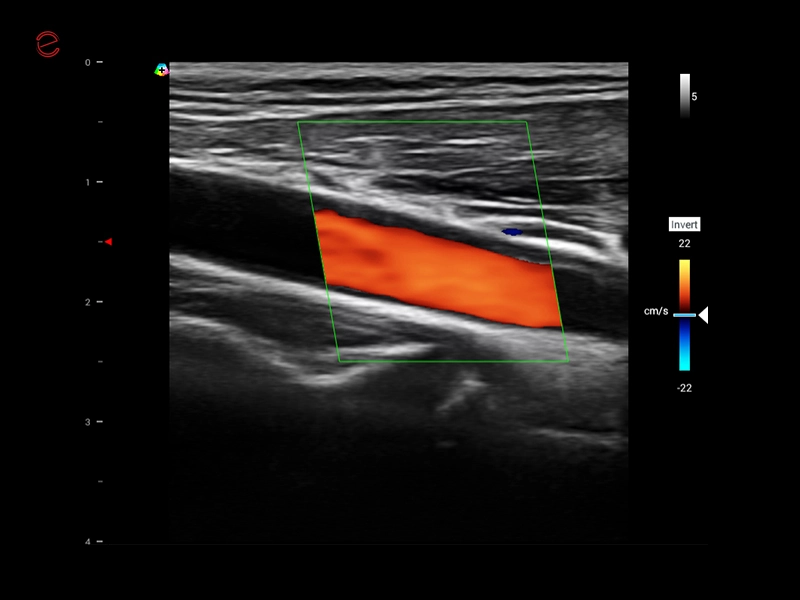

MyLab™X1 Go - CV Doppler 1

MyLab™X1 Go - CV Doppler 1